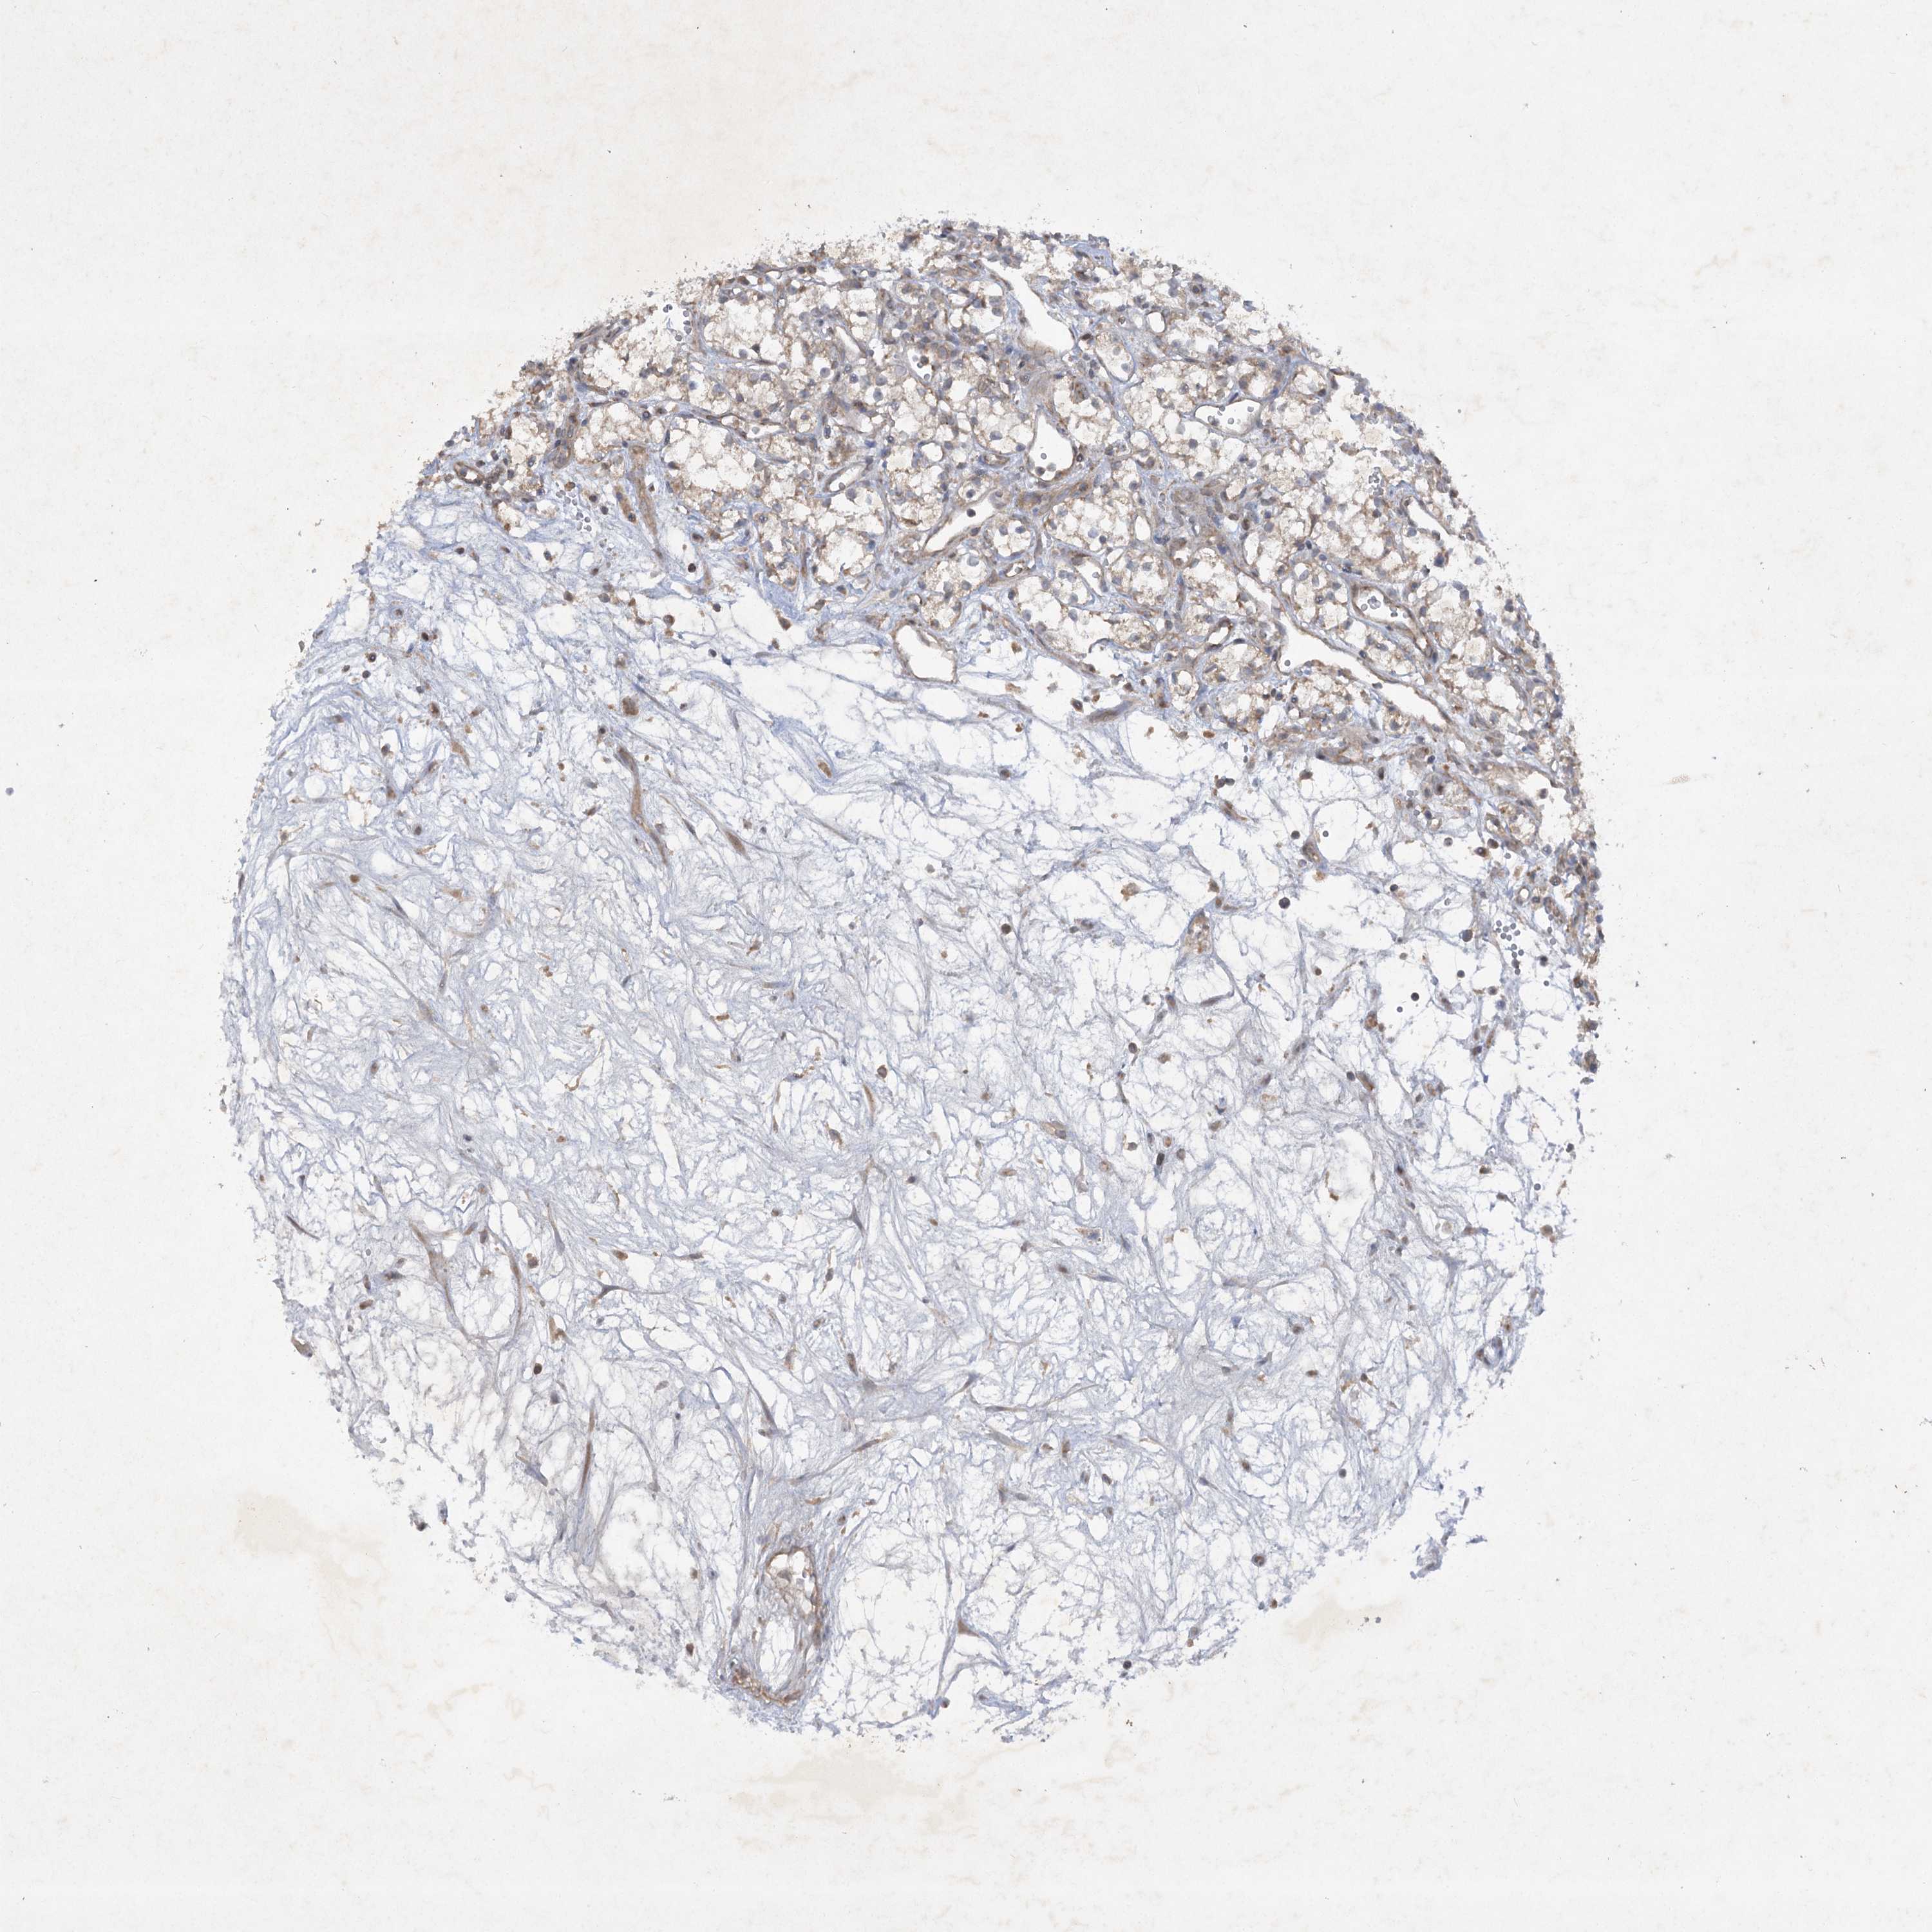

KIDNEY RENAL CLEAR CELL CARCINOMA (TCGA) - Interactive survival scatter ploti

TRAF3IP1 is potential prognostic, high expression is favorable in Kidney Renal Clear Cell Carcinoma (TCGA)

: 5.84

Average pTPM 7.5

Number of samples 521